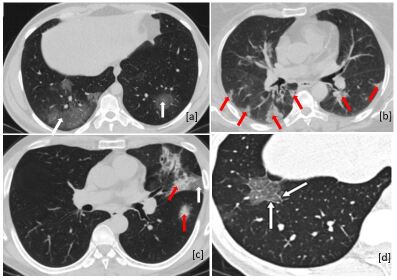

There has been considerable attention on CT imaging as the most useful imaging modality for representing COVID-19 infections. A study [25] on 515151 patients with positive nucleic acid testing reported that only 3.93.93.9% of patients were misdiagnosed based on their chest CT images. Fig. 3 shows common CT patterns in COVID-19 patients, where the most prevalent are “Ground Glass Opacities (GGOs)” and “Consolidations”. GGO is a hazy transparent opacity that does not conceal lung vessels and bronchial areas [26]. In a consolidation pattern, the air in the alveoli and peripheral bronchioles is replaced by fluid such as pus, water, blood, or an inflammatory material, obscuring the underlying distal airways and vascular margins [26]. In a research study on 645645645 confirmed COVID-19 patients, 888888% of patients showed either pure GGOs or consolidation or both [27]. The appearance of pure GGO is more common in the early stage of the disease, while the appearance of GGOs with consolidations is more frequently seen in the progressive stage [28]. Another common CT pattern associated with COVID-19 is the so-called “Crazy Paving” referring to thickened interlobular septa and intralobular interstitium superimposed on GGOs [26]. The crazy paving pattern is more commonly seen in the progressive stage of the disease [28]. The appearance of the crazy paving/consolidation patterns as a sign of disease progression/severity can help radiologists evaluate the disease stage. Interlobular septal thickening, air bronchogram, and vascular enlargement are other CT findings in COVID-19 patients [28].

Refer to caption

Figure 3: The most common CT patterns in COVID-19 patients. (a) Axial CT image of a 38 year-old man with bi-lateral GGOs distributed in posterior lung regions [29]. (b) Axial CT image of a 60-year-old woman, scattered consolidation patterns with mainly peripheral distribution [29]. (c) Axial CT image of a 51-year-old man, the appearance of GGOs (white arrow) and consolidations (red arrows) [29]. (d) Crazy-paving pattern in axial CT image of a 43-year-old woman [30]. All CT images have been obtained without contrast enhancement.

Distribution of Lung Involvement in COVID-19: CT findings of COVID-19 infections demonstrate that most of the COVID-19 patients have had “Bilateral” and “multifocal” lung involvements. Bilateral involvement means that the lesions are distributed in both the right and left lungs, and multifocal involvement implies that more than one lobe (from five lobes) of the lung is affected by the disease. A systematic review of COVID-19 imaging findings [28] declared that in 171717 out of 363636 studies (78.278.278.2%), the number of patients with bilateral lung involvement had been higher than the patients with unilateral involvement.

Researches also showed that COVID-19 lesions in most of the cases are distributed in lower lobes and have a “Peripheral” instead of central distribution [28, 30]. Similarities between CT features of COVID-19 with other viral pneumonia pose limitations in using CT images to diagnose COVID-19. However, in a study of 585858 patients [31], six of seven radiologists could distinguish COVID-19 from other types of viral infections with an accuracy of 6793679367-93% and a specificity of 931009310093-100%. Peripheral distribution and GGOs were the most critical characteristics for distinguishing COVID-19 from non-COVID-19 pneumonia [31].